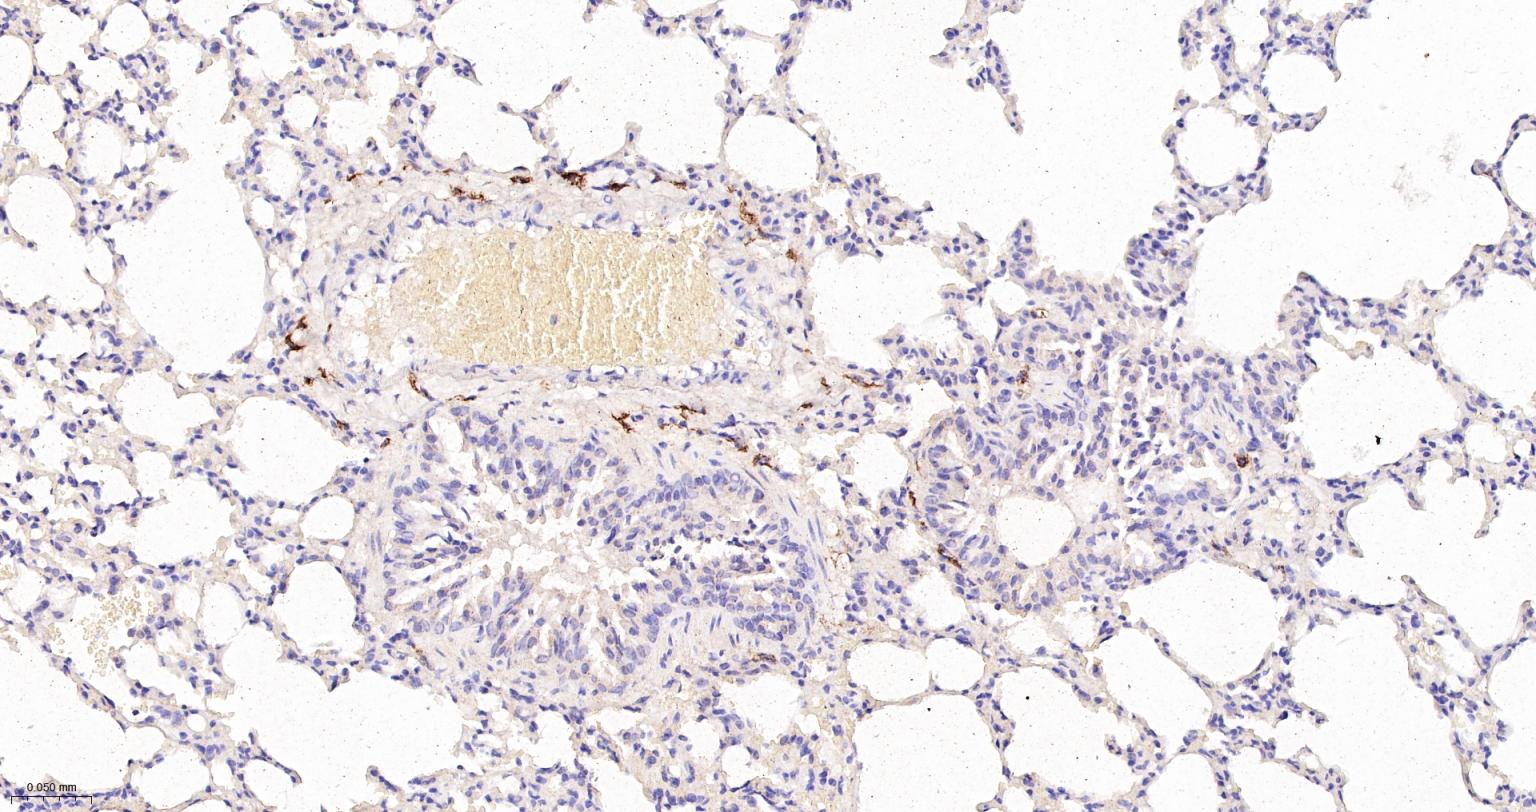

Paraformaldehyde-fixed, paraffin embedded Rat Lung; Antigen retrieval by boiling in sodium citrate buffer (pH6.0) for 15 min; Antibody incubation with CD163 Monoclonal Antibody, Unconjugated(bsm-54015R) at 1:200 overnight at 4°C, followed by conjugation to the bs-0295G-HRP and DAB (C-0010) staining.